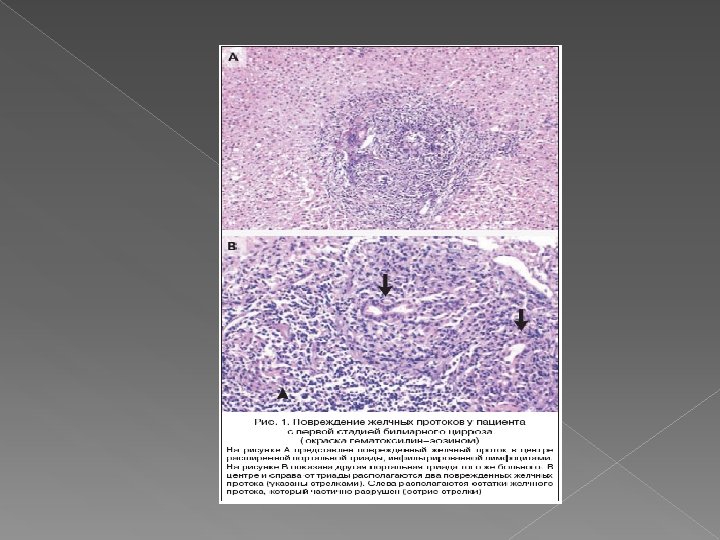

Стадия негнойного деструктивного холангита. Стадия дуктулярной пролиферации с новообразованием желчных канальцев и последующей их деструкцией, что сопровождается разрушением пограничной пластинки портальных трактов воспалительными инфильтратами, ступенчатыми некрозами перипортальных гепатоцитов и холестазом (желчные тромбы в перипортальных канальцах).

Поражение на II стадии со значительными скоп лениями лимфоидных клеток. Начинается пролиферация жёлчных протоков. Окраска гематоксилином и эозином, х10

Воспалительное повреждение желчных протоков (гранулематозная деструкция) при ПБЦ. Плохо сформировавшаяс я гранулема, окружающая и разрушающая желчный проток